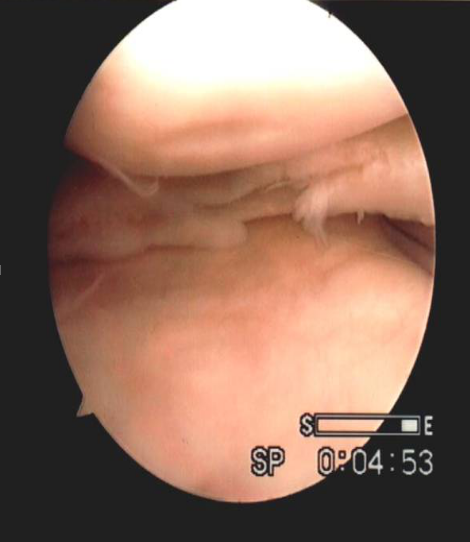

縱裂

橫裂

瓣裂

水平裂

不規(guī)則裂